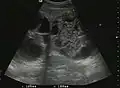

Benign focal nodular hyperplasia (CEUS). Gray scale examination (left) detects the lesion. CEUS examination (right) allows characterization of tumor nature based on central contrast enhancement and centrifugal dispersion.

It is a tumor developed secondary to a circulatory abnormality with abundant arterial vessels having a characteristic location in the center of the tumor, within a fibrotic scar. A radial vessels network develops from this level with peripheral orientation. The tumor's circulatory bed is rich in microcirculatory and portal venous elements. The incidence is higher in younger women and tumor development is accelerated by oral contraceptives intake. 2D ultrasound appearance is a fairly well-defined mass, with variable sizes, usually single, solid consistency with inhomogeneous structure. Rarely the central scar can be distinguished. Spectral Doppler examination detects central arterial vessels and CFM exploration reveals their radial position. CEUS examination shows central tumor filling of the circulatory bed during arterial phase and completely enhancement during portal venous phase. During this phase the center of the lesion becomes hypoechoic, enhancing the tumor scar. During the late phase the tumor remains isoechoic to the liver, which strengthens the diagnosis of benign lesion.